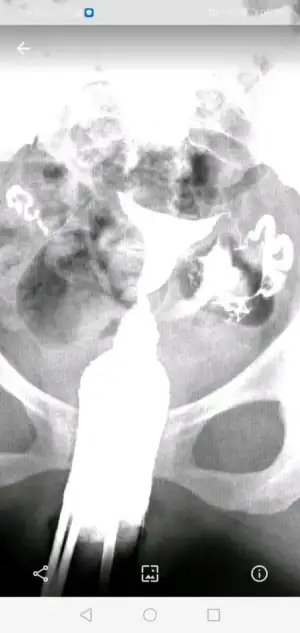

Canım bak 2 ve 3 ilk vuruşlardaki hali en baştaki de 4. Vuruştan sonra çekilen görüntü. Geçiş görünüyor ama açıldı mı bilmiyorum. Doktor lap a gerek yok şuan dedi. 4 ay sonra bi daha hsg çekilcem kendi isteğimleCanım senin tüptekş yapılıklık rahim gilmi ile açıldı mı peki?

Geçiş varsa açılmıştır kuzumCanım bak 2 ve 3 ilk vuruşlardaki hali en baştaki de 4. Vuruştan sonra çekilen görüntü. Geçiş görünüyor ama açıldı mı bilmiyorum. Doktor lap a gerek yok şuan dedi. 4 ay sonra bi daha hsg çekilcem kendi isteğimle

Umarım canım valla çoğu doktor sıkıntı yok yapışıklık varmış açılmış diyor instada bi kadına attım o da tam peritonel geçiş yok gibi falan dedi ama ben yine aşılamadan önce çekilcem hsg bi son hali ne durumda göreyimGeçiş varsa açılmıştır kuzum![]()

Açılmış canım geçmiş sıvı karın boşluğuna iki taraftan daCanım bak 2 ve 3 ilk vuruşlardaki hali en baştaki de 4. Vuruştan sonra çekilen görüntü. Geçiş görünüyor ama açıldı mı bilmiyorum. Doktor lap a gerek yok şuan dedi. 4 ay sonra bi daha hsg çekilcem kendi isteğimle

Umarım canım ben de öyle düşünmek istiyorumAçılmış canım geçmiş sıvı karın boşluğuna iki taraftan da